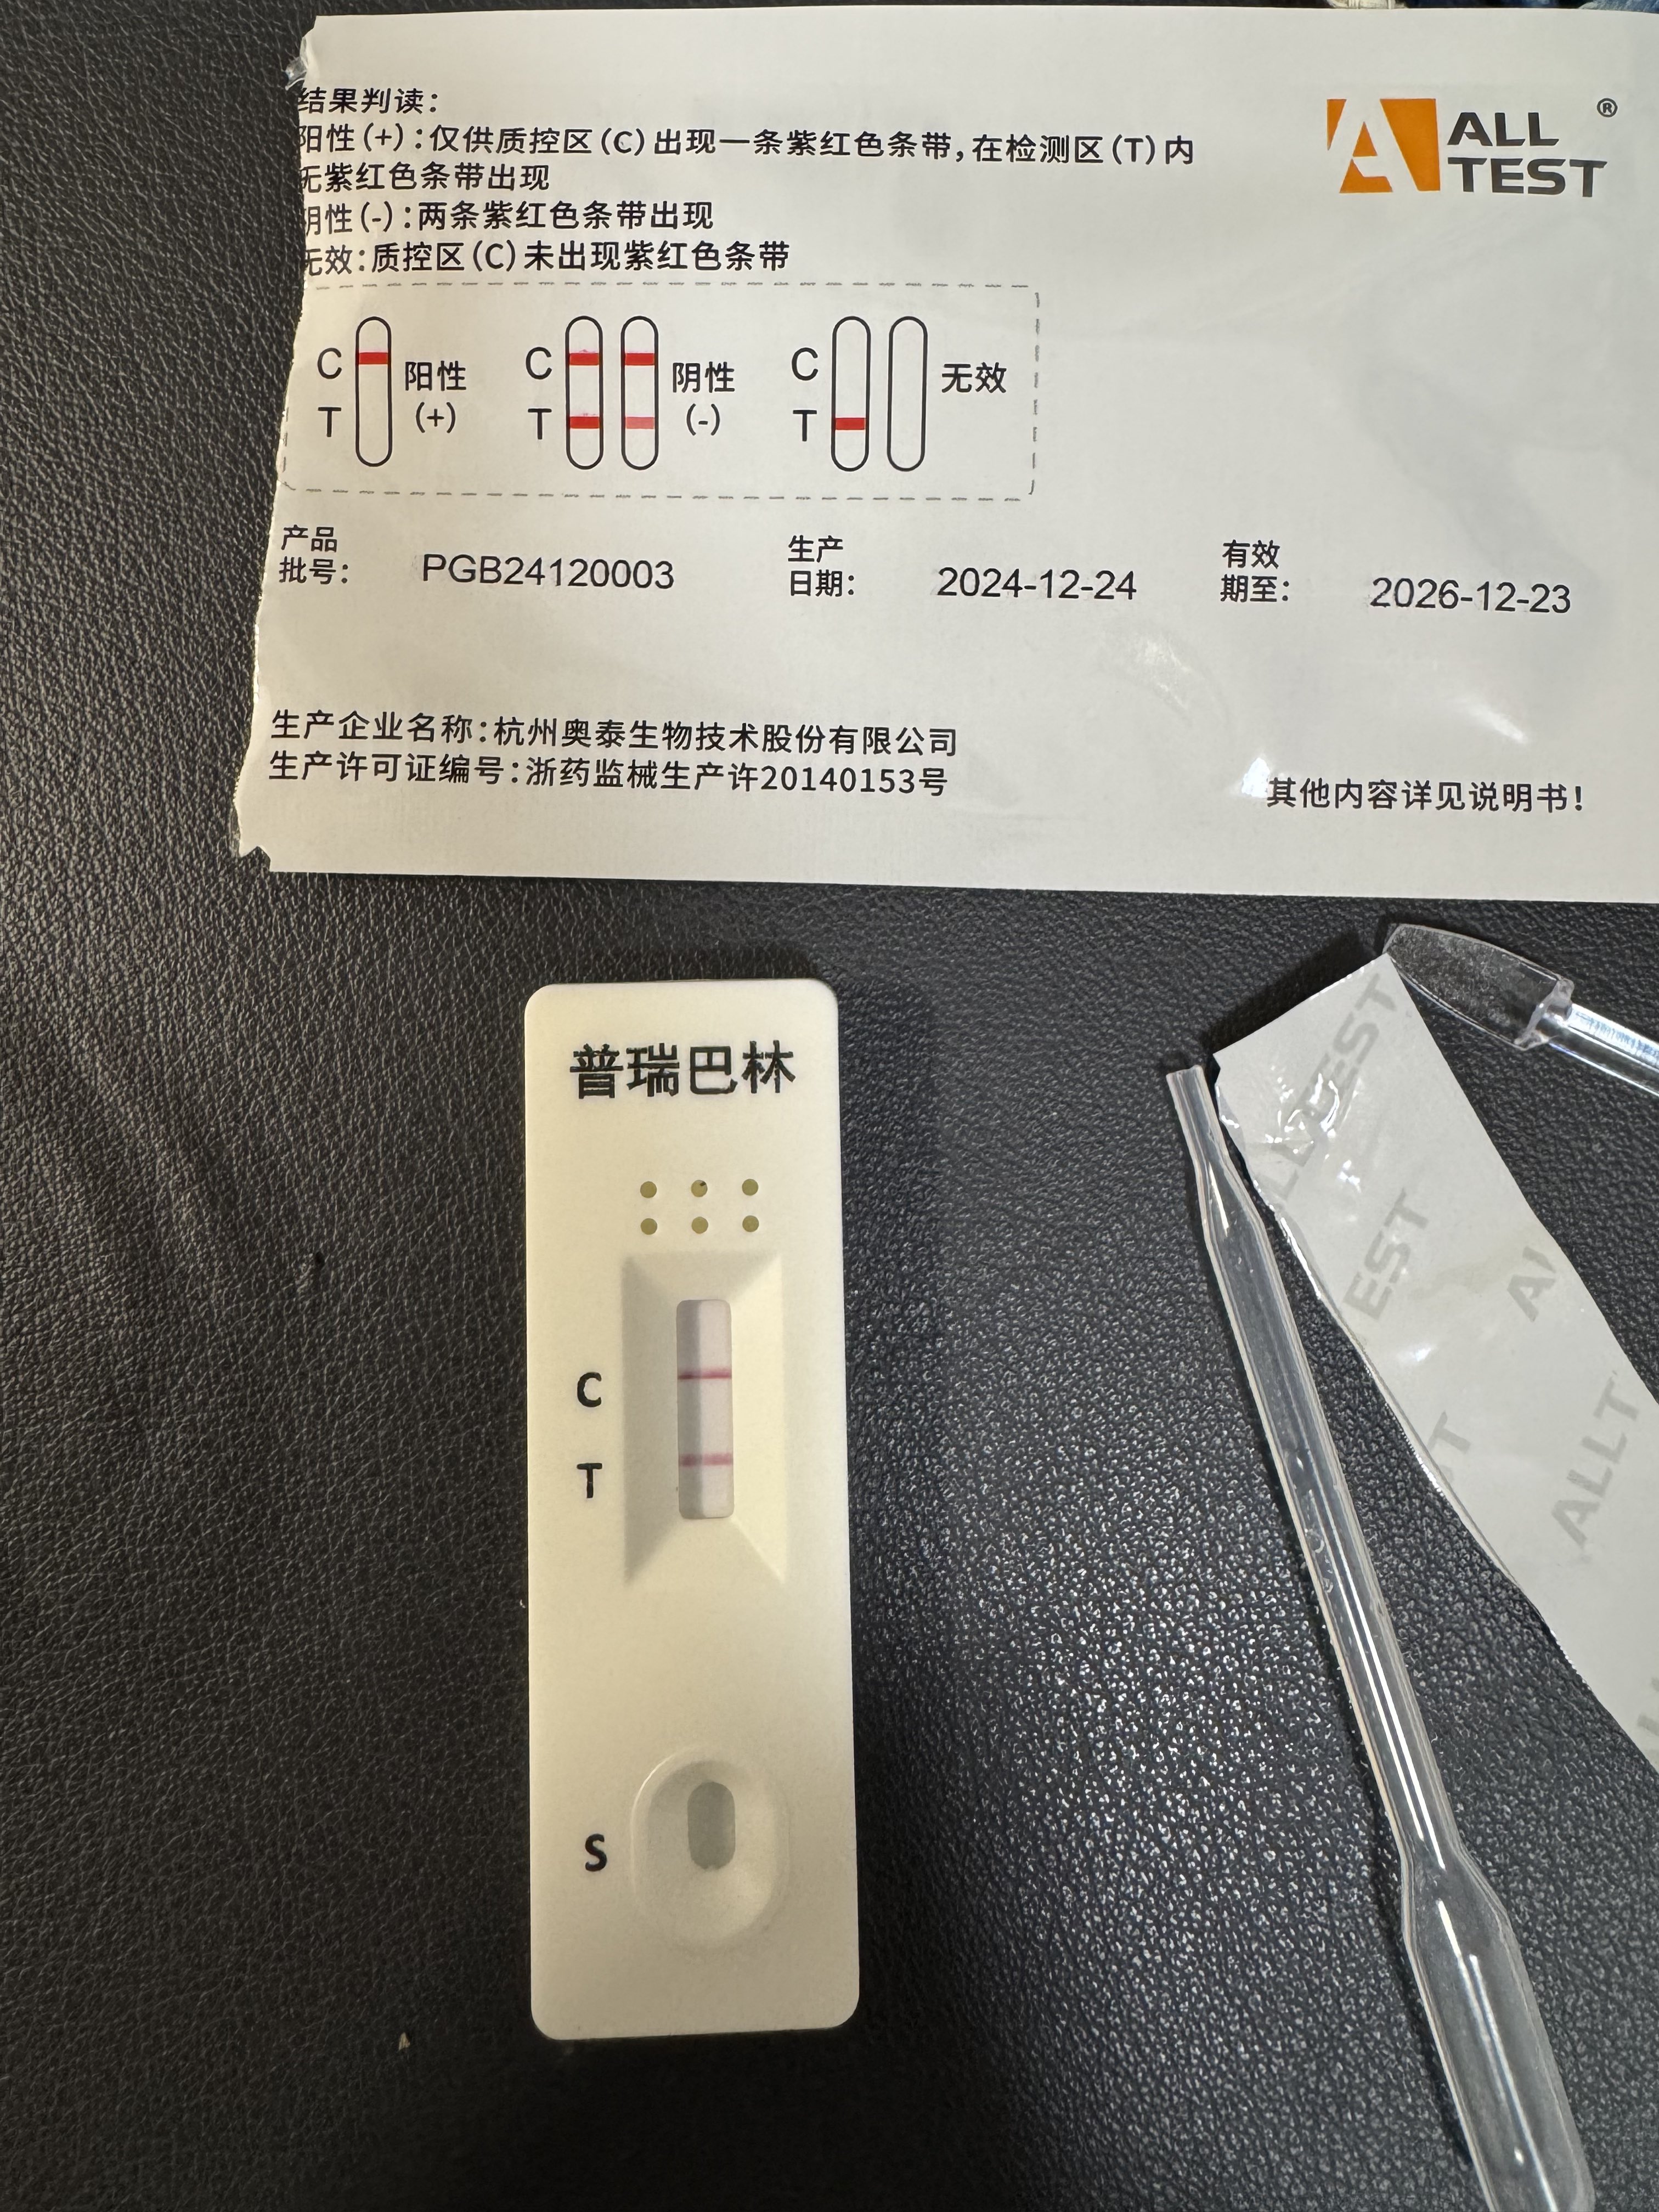

甚至在第二天有余晖的感觉,虽然发生了很多破事但没怎么影响心情*抗焦虑&镇静

运动协调性稍差,表现为走路和站立时平衡不好

此剂量下对睡眠的改善作用,增加了慢波睡眠且没有影响rem,精力恢复+

FDA数据,在临床剂量下(75-600mg)普瑞巴林的依赖性低于bzd,并相比之下它产生的认知和精神运动障碍较轻 https://t.co/TJ7ZOQ7pbC